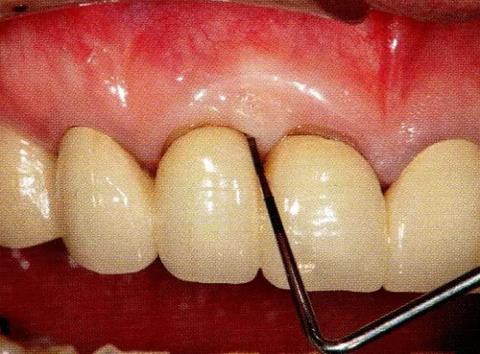

▼圖13-6 術(shù)后8個月的狀態(tài)。牙周探診值改善到4mm,牙齦萎縮基本沒有出現(xiàn)。進(jìn)行GTR法時,上頜顎側(cè)牙齦容易出現(xiàn)壞死,但是使用EMD促生長因子處理時,不容易出現(xiàn)牙齦壞死和退縮。